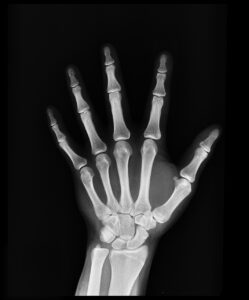

ACL断裂は、前十字靭帯が完全に切れてしまう状態を指します。この靭帯は、膝関節の安定性を保つ重要な役割を果たしており、特にサッカーなどのスポーツでは、その機能が非常に重要です。

ACL断裂の主な原因は、急な方向転換や不適切な着地、過度なストレッチなどです。サッカーでは、ドリブルやシュート、ディフェンスの動作の際にこれらの動きが頻繁に行われるため、選手は特に注意が必要です。